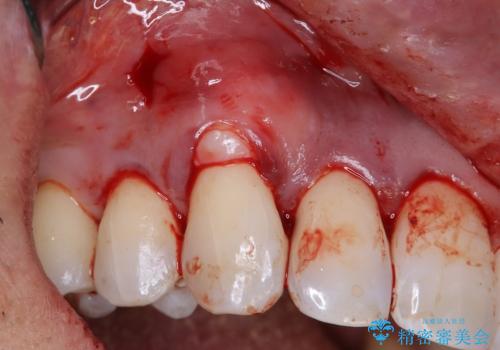

- 歯肉退縮にお悩みの患者様に対して、根面被覆術(結合組織移植術)を行いました。

歯肉移植(結合組織移植術)とは、患者様ご自身の歯肉を移植することで、後退した歯肉を補う治療法です。具体的には、上あごの内側から採取した健康な歯肉を、歯肉退縮が見られる部分に移植します。この手術により、後退した歯肉が再び歯の根元を覆うようになり、見た目も改善されます。